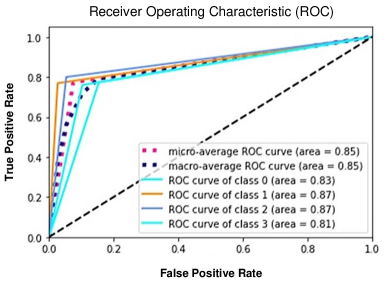

We trained a convolutional neural network (CNN) to classify four severities of burns: SPF (superficial), SPT (superficial partial thickness), DPT (deep partial thickness), and FT (full thickness). We built a saliency mapping method, Boundary Attention Mapping (BAM), that utilises this trained CNN for the purpose of accurately localizing and segmenting the burn regions from skin burn images. We demonstrated the effectiveness of our proposed pipeline through extensive experiments and evaluations using two datasets; 1) A larger skin burn image dataset consisting of 1684 skin burn images of four burn severities, 2) An LDI dataset that consists of a total of 184 skin burn images with their associated LDI scans. The CNN trained using the first dataset achieved an average F1-Score of 78% and micro/macro- average ROC of 85% in classifying the four burn severities. Moreover, a comparison between the BAM results and LDI results for measuring injury boundary showed that the segmentations generated by our method achieved 91.60% accuracy, 78.17% sensitivity, and 93.37% specificity.

The Boundary Attention Mapper (BAM) methodology of creating saliency maps, dependent on information in various layers of a convolutional neural network (CNN), allows us to generate fine-grained segmentations of the burn injury from images. We trained a CNN, with a pre-trained EfficientNetB7 architecture, on 1684 burn images, to classify four severities of burns: SPF (superficial), SPT (superficial partial thickness), DPT (deep partial thickness), and FT (full thickness). The CNN achieved an average F1-Score of 78% (Table 1) and micro/macro- average ROC of 85% (Figure 1a). A confusion matrix illustrates true and predicted values, therefore illustrating the true positive and negative error rates of the system. The matrix identifies that misclassification between burn severity classes is highest between adjacent classes of severity, for example SPT and DPT (Figure 1b).